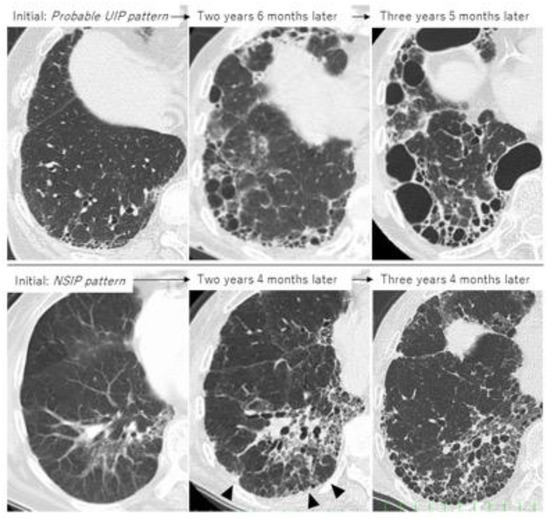

4.2. Disease Behavior

4.3. Predictors of ILD Progression and Prognostic Factors